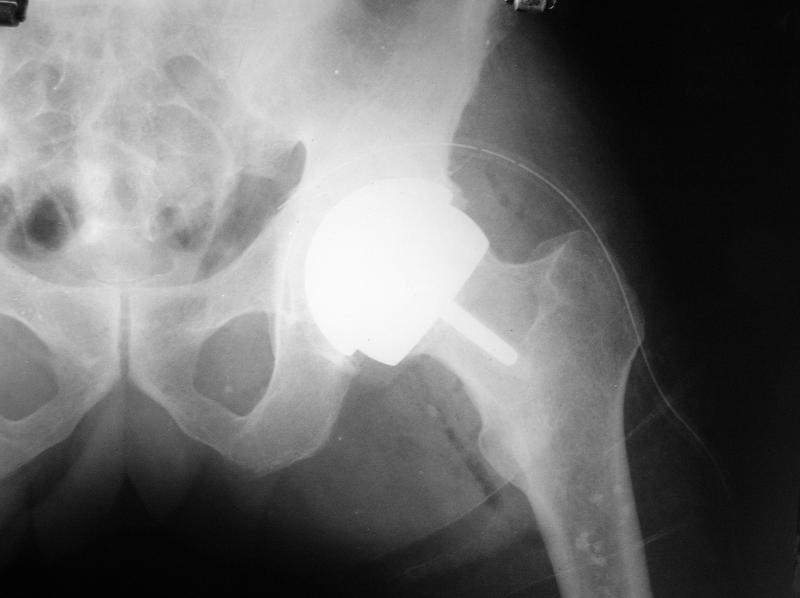

Surface Replacement of hip